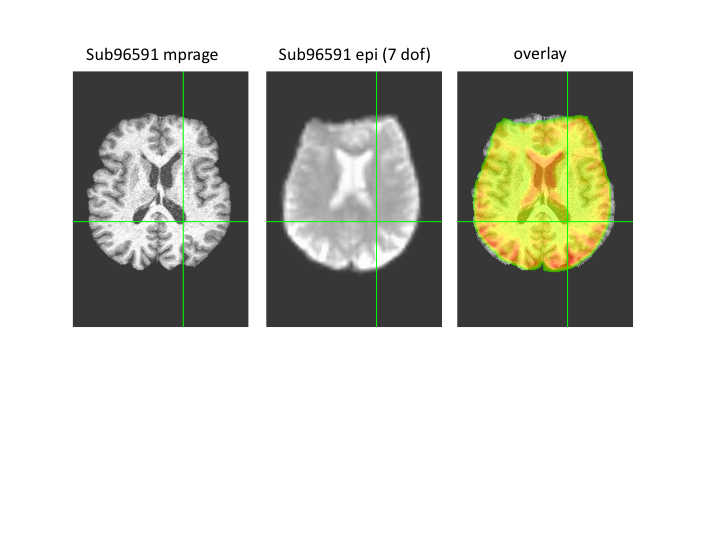

Regarding sub96591. We backtraced our steps and realized we used a 7 DOF linear EPI to skull-stripped MPRAGE for the images in the paper. However, the 7 vs. 6 DOF is not the full solution. If you look in our preprocessing scripts, you can see that we get the example func image that is used for later registration after skull-stripping the EPI. If you use the skull-stripped EPI in combination with the 7 DOF FLIRT registration the alignment appears to be good. I attached an image comparing 6 DOF to 7 DOF and 7 DOF on the skull-stripped EPI for this subject. The differences in results are pretty clear.

As to why 7 DOF appears to work better, one possibility is that some degree of scaling may have occurred for the EPI on the scanner. As indicated before, we are not sure whether the EPI and MPRAGE for these subjects were collected on the same day.

I'll try and convince you with one more image. I ran flirt with 7 dof on a skull-stripped epi for sub96591.

Three images are attached.

1. epi aligned to mprage (slice 146)

2. mprage (slice 146)

3. overlay with 50% transparency.

I've put the cross-hair at the edge of the posterior extent of the left lateral ventricle. The cross-hair is displayed for the same coordinate on the epi. Look at the shape of the ventricles and the position of the cross-hair. The overlay looks OK because the extra dof corrects for overall differences in brain size and its hard to see the differences in detail (e.g. shape of ventricles). My sense is that these are two different brains.